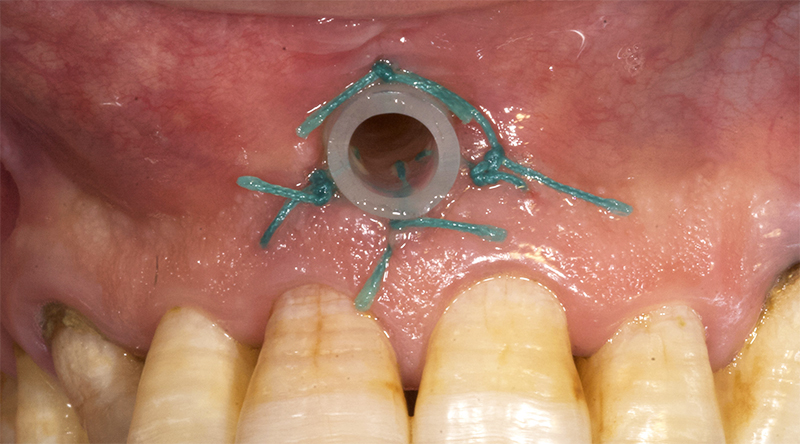

Ainsi, certains auteurs(8) proposent de réaliser une décompression avec mise en place d’un drain associée à une biopsie d’une partie de la lésion. Cette alternative thérapeutique a pour but de diminuer la taille de la lésion et donc d’intervenir plus tard (en général 3 à 6 mois voire 1 an pour les lésions les plus volumineuses) sans risque pour les structures nobles (dents, nerf alvéolaire inférieur et mandibule).

Cette thérapeutique est néanmoins controversée car elle présente deux désavantages : la nécessité d’une collaboration très importante de la part du patient (suivi régulier et irrigation biquotidienne à la chlorhexidine du drain par le patient) et le prélèvement d’un échantillon de la lésion qui ne met pas à l’abri de se trouver en présence d’une tumeur maligne sur une autre partie de celle-ci.

Fig. 03 : exemple de drain de décompression, mis en place dans le fond du vestibule antérieur afin de diminuer la taille de la lésion osseuse sous-jacente. Pour maintenir le drain en place, celui-ci est suturé à l’aide de fil de suture non résorbable (ici Mersuture, Ethicon® 4/0).

Compte tenu de l’importance de la lésion, et afin de proposer au patient une thérapeutique la plus conservatrice possible, il est donc proposé de réaliser cette technique par décompression de la lésion associée à une biopsie d’une partie de la lésion.